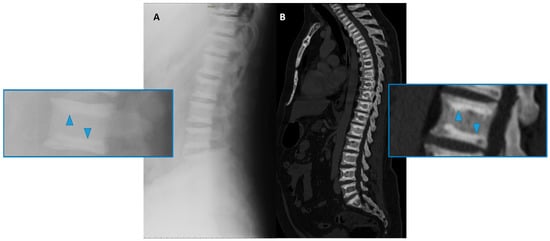

(4) Well-defined sclerosis and the thickening of the vertebral endplate, the so-called “sandwich vertebrae” (Figure 4), and the ill-defined increased density of the vertebral endplates at multiple contiguous levels, the so-called “rugger-jersey” spine, which is, however, more typical of hyperparathyroidism [25,26]; this sign is more frequently encountered in ADO type 2 osteopetrosis.

Figure 4. Conventional radiography (lateral projection, (A)) and Computed Tomography (CT Sagittal reconstruction, (B)) of the spine of a 50-year-old male affected by osteopetrosis (ADO type 2). Well-defined areas of increased bone density are detectable on the vertebral endplates (arrowhead), configuring the so-called ‘sandwich vertebrae’ appearance.